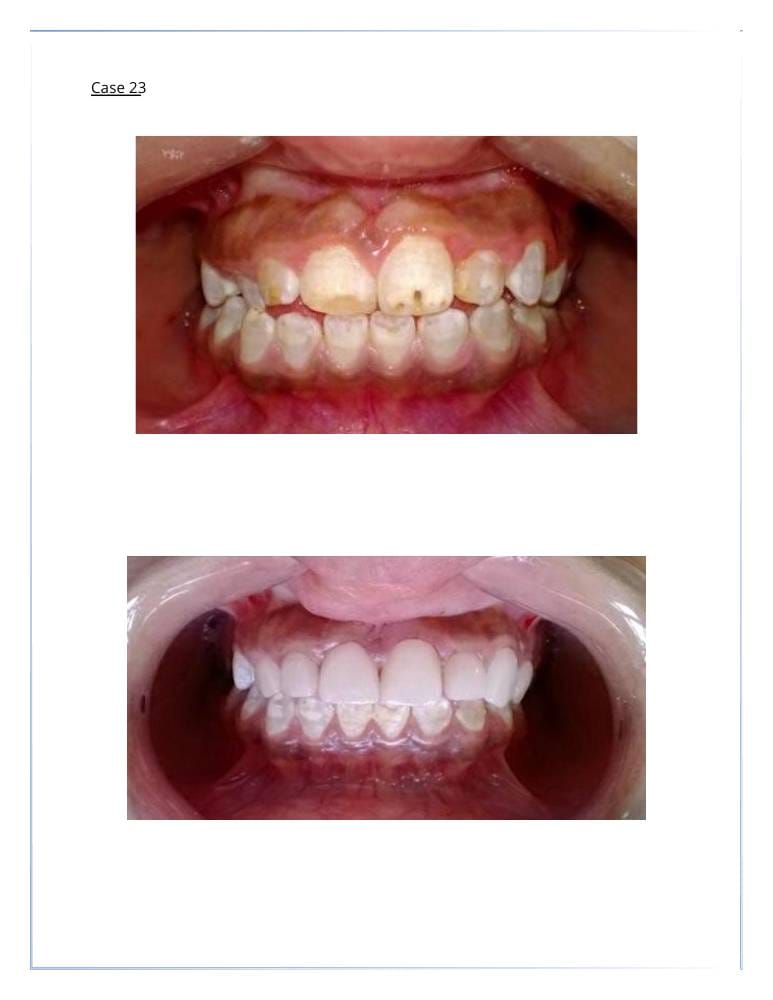

التجميل السني

- اكدت الدراسات ان شكل ولون الاسنان يساهم في تغيير شكل وجمال الوجه بنسبة 47%

تبييض الأسنان. - قشور الفينير (veneer) لتغطية الأسنان المعيبة.

- إعادة تشكيل وتعديل الأسنان لتحسين المظهر.